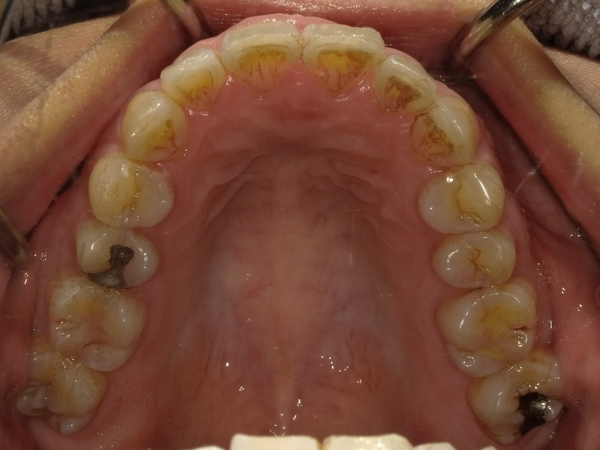

◯ご相談内容:歯がでたり引っ込んでいたりする◯矯正の種類:マウスピース型矯正「インビザラインGO」◯治療期間:17週間◯治療費用:44万円(税込)